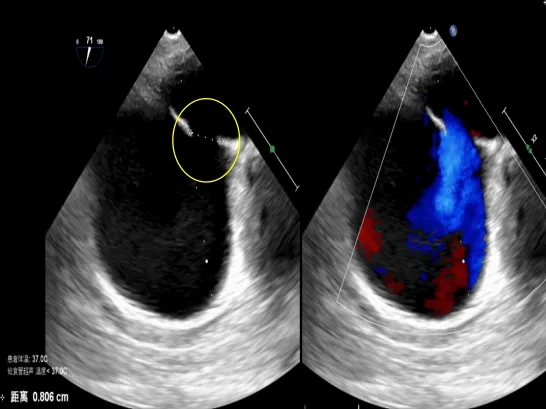

经食道超声可见

第一个缺损8.06mm

术中超声:术中经食道超声可见有两个缺损,分别为8.06mm、5.63mm,和术前超声报告对比有所偏差,两缺损距离约8.48mm。